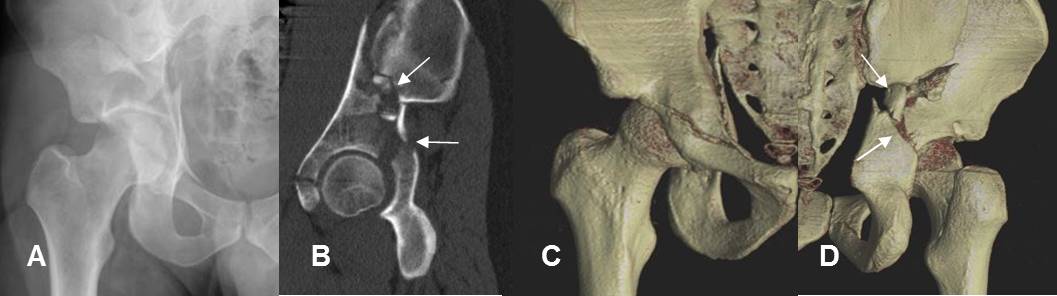

Fig 22. TAC con reconstrucción 3 D.

A: Rx AP y B: TAC reconstrucción sagital. Fractura conminuta e impactada del techo acetabular.

C: TAC reconstrucción 3D vista anterior y D: vista posterior. Se puede identificar que el compromiso del techo acetabular, compromete predominantemente la parte posterior.